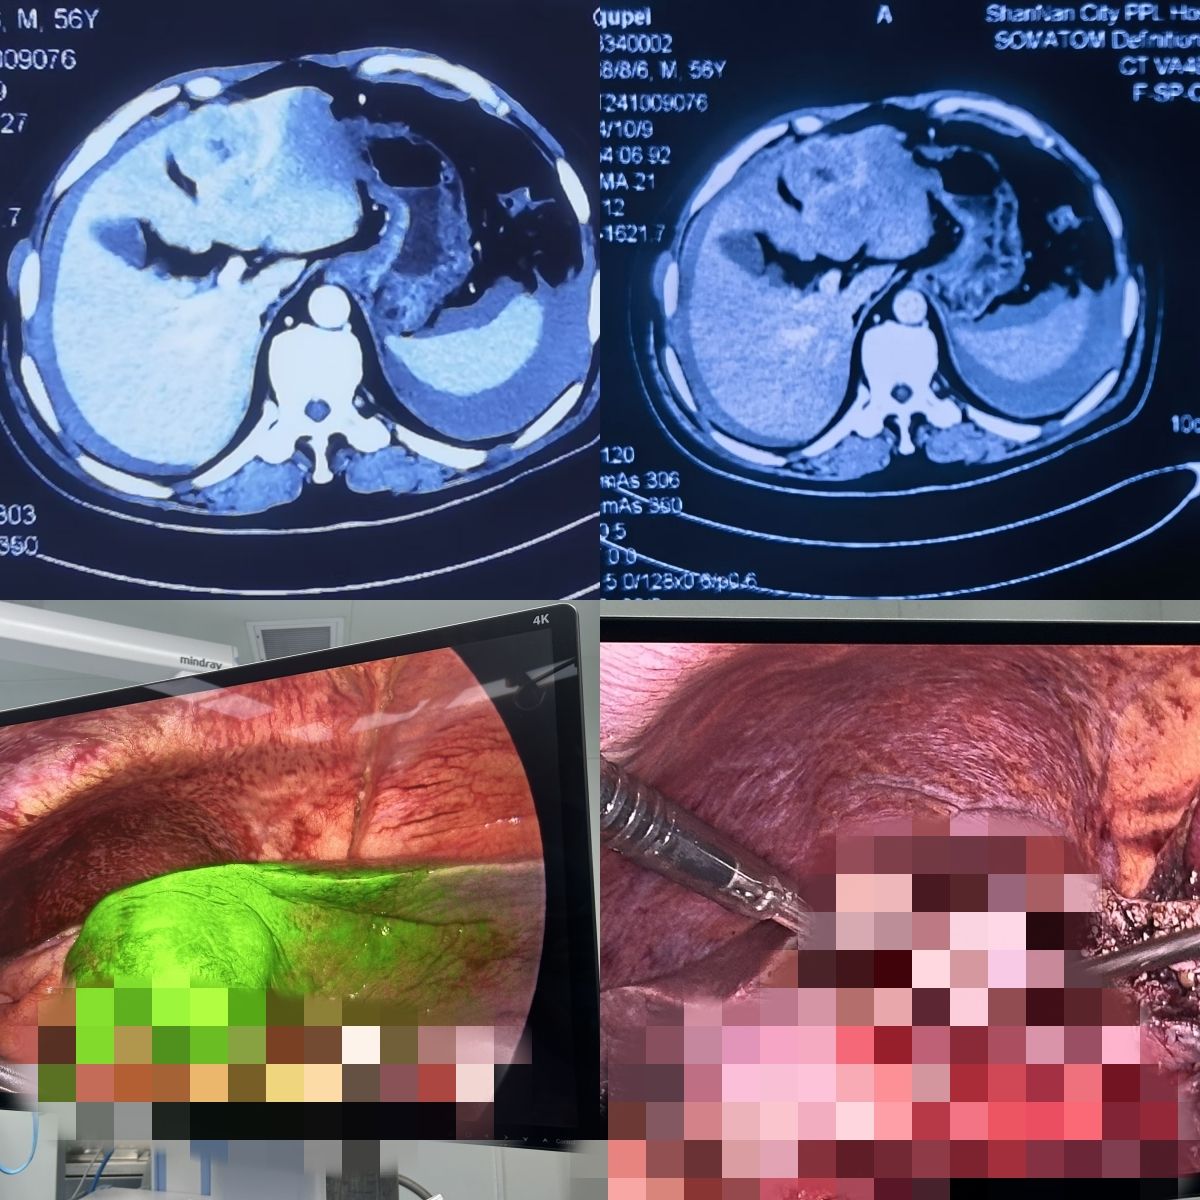

ICG(吲哚菁绿)荧光引导下腹腔镜肝癌切除手术

患者男性,56岁,因上腹部疼痛不适在山南市人民医院就诊,门诊彩超提示肝脏占位,腹腔积液(考虑肝ca破裂出血,出血已停止),住院后积极对症处理,完善检查肝脏肿瘤位于肝脏ⅣB段,未见肝内及远处转移。经过充分术前准备,援藏医疗专家方小三实施ICG(吲哚菁绿)荧光引导下腹腔镜肝癌切除手术,肿块完整切除,术后患者恢复良好,患者顺利出院。